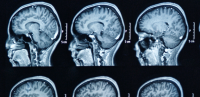

The role of the neuroradiologist is critical for neurosurgical patient care. Columbia Neurosurgery works with some of the most experienced and specialized in the field to provide a comprehensive and interdisciplinary approach to care. A neuroradiologist obtains further training in treating the spine, head, neck and the central and peripheral nervous systems. The Neurological Institute of New York here at CUIMC was the first hospital in the western hemisphere dedicated to neurosurgery and radiology. Through the last 100 years, the team has evolved into a highly specialized model with key radiology team members serving each division.

Says Dr. Raymond Sekula, "When working with our neuroradiologists, I am energized by the fact that we have developed the highest resolution MRI and other protocols available in the United States, which has dramatically transformed our ability to care for patients with hard to reach skull base tumors, including meningiomas, acoustic neuromas, and other disorders as well as cranial neuralgias, such as trigeminal neuralgia, hemifacial spasm, and glossopharyngeal neuralgia. With patients traveling each week from across the U.S. for our services, we provide top-of-class neurosurgical care."

Concerning functional brain mapping, Dr. Brett Youngerman shared, "We are deploying the latest advanced imaging techniques for targeting difficult-to-see structures in the brain and avoiding function critical sites. Advanced structural imaging techniques and diffusion tensor imaging, also known as tractography, allow us to target millimeter-sized structures deep in the brain that were previously not visible but are essential for outcomes of neuromodulation therapy for drug-resistant epilepsy and Parkinson's disease. Advanced imaging also allows us to identify the onset of seizures in drug-resistant epilepsy. Other functional imaging techniques allow us to protect critical functions like speech, motor, and vision."